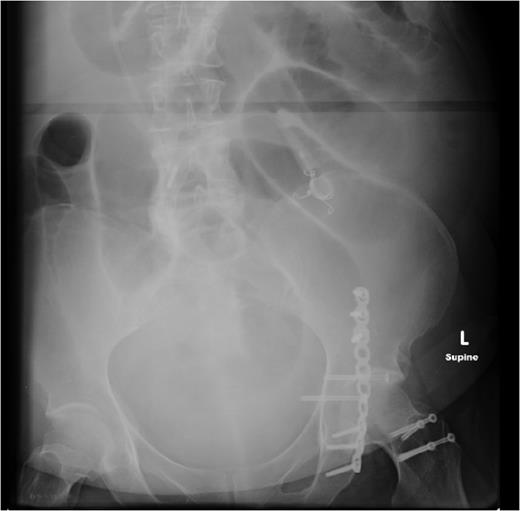

Two weeks later, she re-presented to the emergency department with a 24-hour history of severe central abdominal pain associated with vomiting and multiple episodes of loose stools. On examination, she was found to be hypotensive, tachycardic and peritonitic. The suspicion of an SBO was established by plain film radiograph appearances with multiple air fluid levels and distended bowel loops (Fig. 1). Computed tomography scan of the abdomen and pelvis showed the transitional zone to be in mid abdomen (Fig. 2). This was thought to be most likely secondary to adhesions. She proceeded on to have an emergency laparoscopy. Interestingly, the laparoscopy identified the transition point of the SBO to be an adhesion formed between the LAGB tube, the mid jejunum and the stomach forming a classic closed-loop obstruction (Fig. 3). The laparoscopic division of this adhesion was performed successfully. The rest of the small bowel was run along its entire length with no other transition point found. The adjustable gastric band was removed at the same time along with the associated port. Postoperatively, she had an uncomplicated recovery and was discharged on Day 4 post-admission without further sequelae.

Computed tomography reconstruction showing the SBO with transition zone in the mid ileum, later discovered to be caused by gastric band tubing (T).